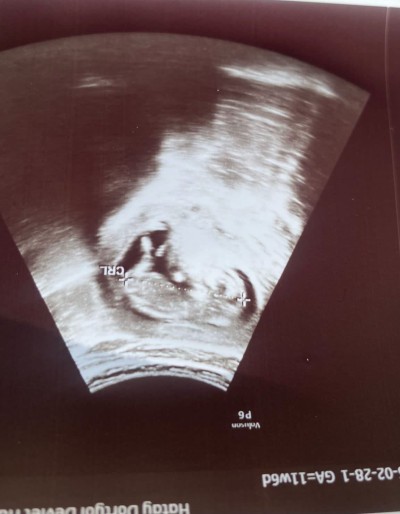

Cinsiyet tahmininde bulunurmusunuz hanimlar 12+ 3 de alinan goruntu

Gebelik haftası 13+4

Erkek gibi hissettim

Bacak arası kapalı ama sanki kız gibi duruyor tm emin değilim sadece tahmin